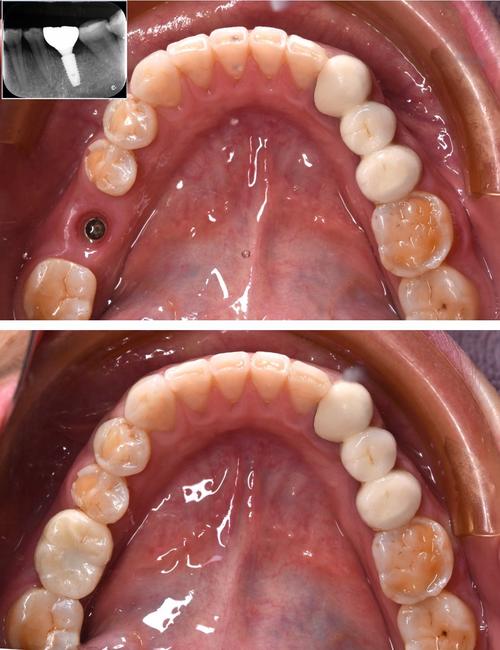

种植体周围骨吸收(在X光片上可见):

(图片来源网络,侵删)虽然患者自己无法直接看到,但医生通过拍摄X光片,可以观察到种植体周围的骨头出现吸收、破坏的迹象(骨结合失败的表现)。

后期失败的主要影像学表现,定期复查拍X光片是早期发现骨吸收的关键,骨吸收达到一定程度会导致种植体支持力不足,最终松动。